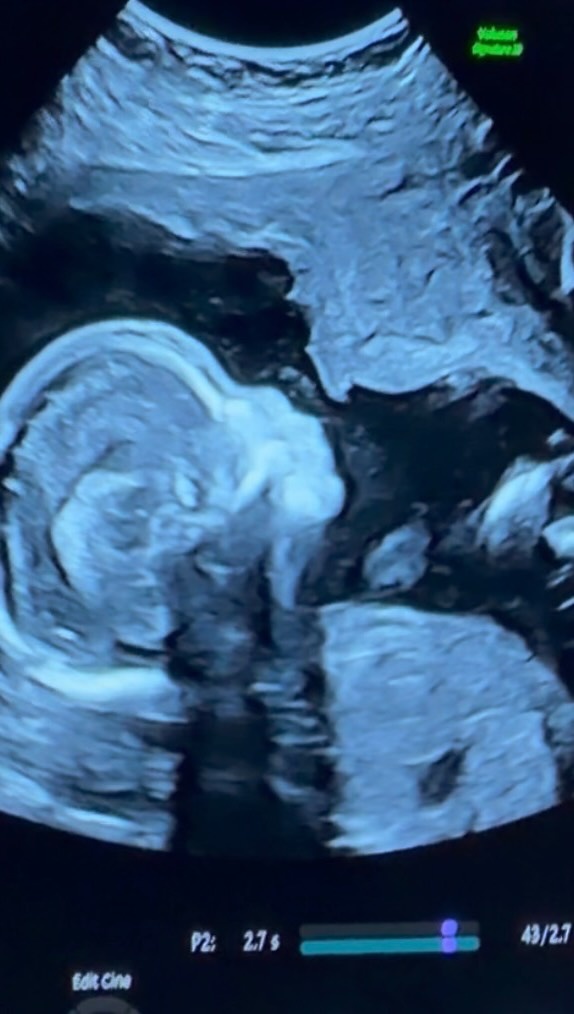

直播吧2月19日讯 索汉女友友Mya Mills更新社媒,晒出了自己做孕期彩超的动态,她配文写道:“没有比这更好的感觉了。”

值得一提的是,在前两天,她也晒出了一条动态,记录了怀孕几个月的一些点滴,还写道:“怀着你已经5个月了,距离把你抱在怀里正好走到一半。这并不是我原本设想的公布方式,但有些事情,总会在对的时间浮出水面……这只会让我变得更强大,很快见面,我的小宝贝 🎀👸🏽🩷”